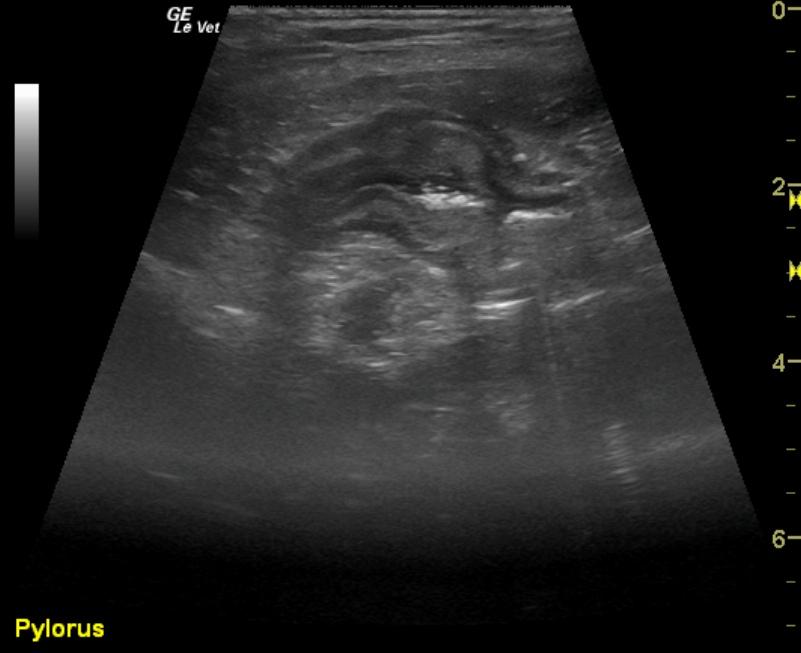

Pyloric outflow was mildly prominent in this patient with hypertrophy of the muscularis and mildly increased echogenicity of the submucosa layer. The remainder of the intestinal tract revealed thickened submucosal layers. Jejunal lymph nodes were enlarged at 2.87 x 1.47 cm with uniform contour, and the egg shape formation would be more suggestive of reactive lymphadenitis.